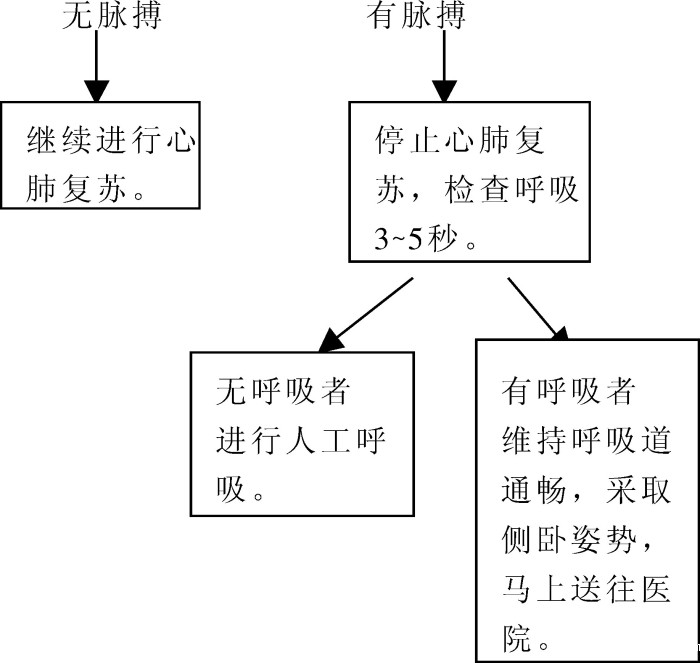

约一分钟后(如8重复四次),检查脉搏的有无。

若